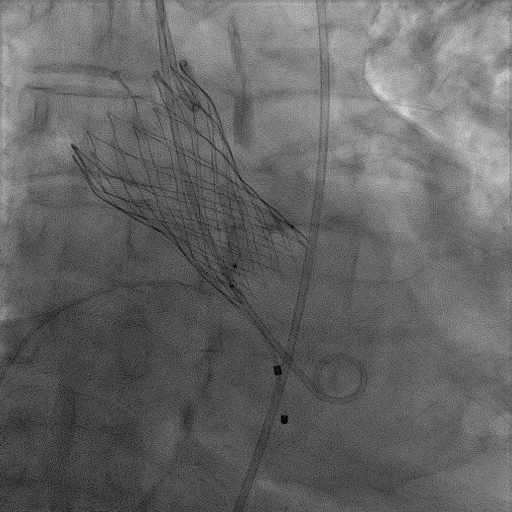

手术过程

患者麻醉方式为全麻,建立静脉通路后,穿刺右侧股静脉,预埋ProGlide缝合器,食道超声指导下房间隔穿刺成功,将Superstiff导丝送至左房,应用18F鞘管扩张穿刺部位,沿导丝将导引导管送入左房,MitraClip调整后顺利到达二尖瓣目标位置,在X线及食道超声辅助下,将Mitraclip NTR成形夹精确定位后,成功夹合二尖瓣A2-P2区,超声显示反流明显减少,多切面证实夹合组织充分,肺静脉多普勒波形由反向恢复正常,手术顺利结束,安返普通病房。

3D视图下观察二尖瓣双孔形态

3D-color:残余少量返流

自2021年5月,安贞医院心脏瓣膜病介入中心以一天内完成3台TAVR手术标志心脏瓣膜中心正式投入工作以来,此例MitraClip二尖瓣修复术已是团队陆续成功完成的第四例MitraClip手术。

此例二尖瓣修复术虽然存在一定的难度和复杂之处,但团队在面临MitraClip时已不再是“初生牛犊”,此次整个手术过程团队整体配合默契,操作流程顺畅。手术过程也相对较快,患者术者身体情况大幅好转,症状明显改善;可以说团队在处理复杂二尖瓣反流患者方面已达到了较高水准。